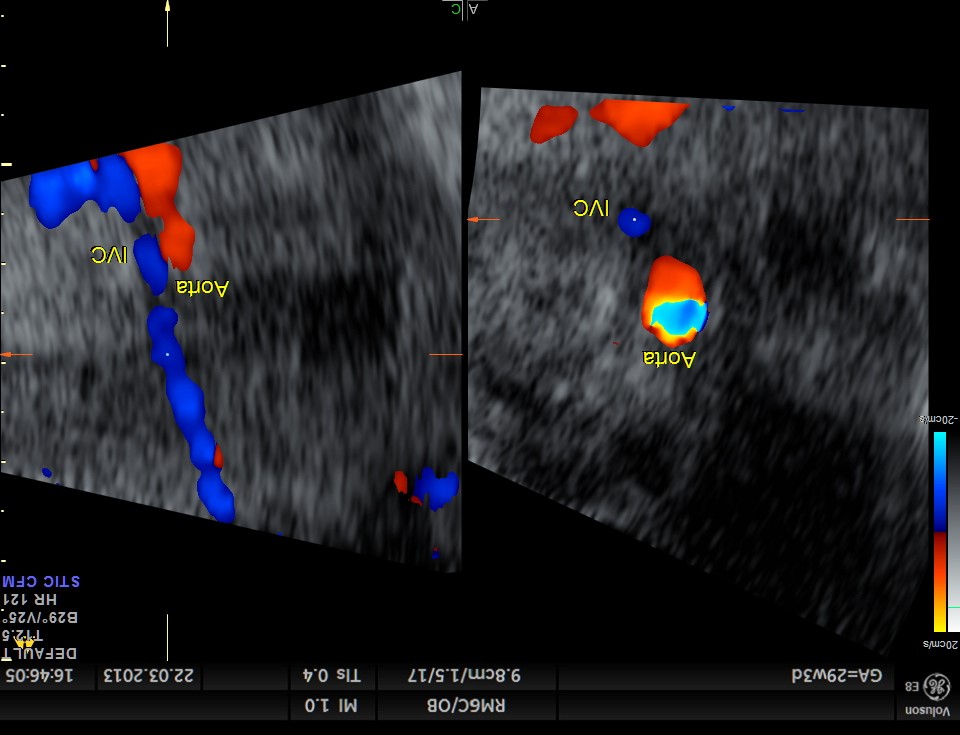

The relationship among the inferior vena cava, aorta, and spine displayed by ultrasonography has been shown to be a reliable method to diagnose situs in the newborn. This technique can be applied to the fetus in utero as well.

Normally, the aorta lies to the left of the spine and the inferior vena cava lies to the right. The following image shows the normal situs in a fetus , with head in upper pole.

Right isomerism or asplenia is suggested when the aorta and vena cava are found together on the same side of the spine.

Particular to the diagnosis of Left isomerism or polysplenia syndrome is the demonstration of inferior vena caval interruption with azygos continuation.

double vessel sign seen in front of spine

two splenic arteries are seen running backwards – indicating polysplenia

double vessel sign seen behind the heart

1. double vessel sign of aorta and azygos vein running side by side , with azygos slightly posterior,